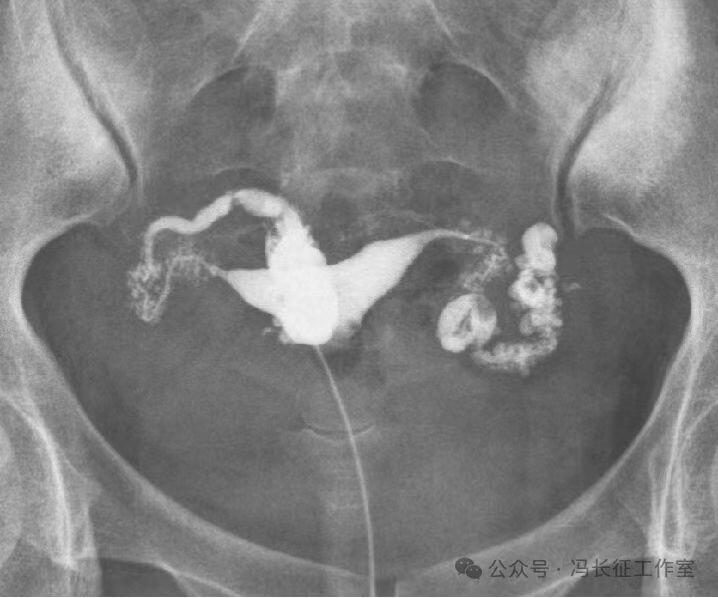

输卵管积水的子宫输卵管造影尽量包括这5个方面的描述,诊断的临床意义才最大,这样才能给好的生殖科医生有价值的建议,帮助给不孕者制定最好的助孕治疗方案。比如这例输卵管积水,峡部结节性输卵管炎(病因),交通性(积水近端是否和宫腔相通),中度(积水大小),厚壁(管壁的厚度),多囊(囊腔的多少)。

微信图片_20240220111130(2).jpg

最后诊断应该是:双侧峡部结节性输卵管炎并双侧中度、厚壁、多囊、交通性输卵管积水。